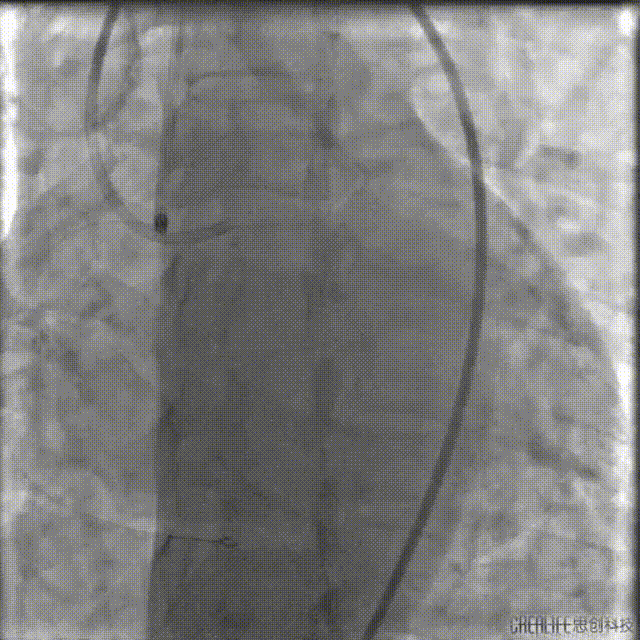

由远及近串联植入2.5*36mm、2.75*36mm、3.5*29mm支架三枚。

支架释放后造影,中段支架膨胀欠佳。

IVUS查看见支架远端局部血肿,遂远段植入2.25*29mm支架,并送入2.5*15mm球囊后扩,并用4.0*12mm球囊后扩近段支架。

最终造影结果

复查造影未见明显狭窄,TIMI血流3级。